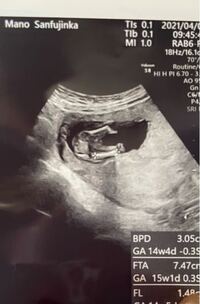

妊娠14週 エコーで性別がわかる お腹の大きさは こそだてハック